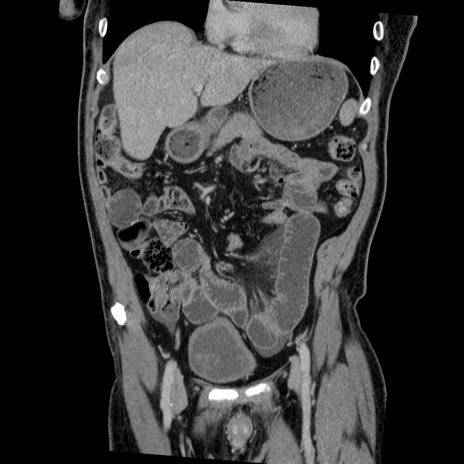

症例22(冠状断像)

【症例】50歳代男性

【主訴】腹痛

【現病歴】AVMからの被殻出血のため回復期リハ病棟入院中。 本日午後3時頃急に下腹部痛が出現した。

【既往歴】AVM、被殻出血、虫垂炎、高血圧

【身体所見】意識晴明、左半身不全麻痺、会話の理解は良好、36.5°C、腹部:膨隆、全体に板状硬、下腹部正中に圧痛点あり、反跳痛-、筋性防御不明、右下腹部にope scar

【データ】WBC 9400、CRP 0.06